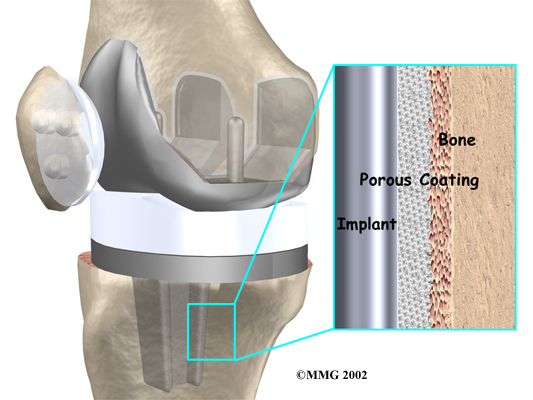

A is held in place by a type of epoxy cement that attaches the metal to the bone. An has a fine mesh of holes on the surface that allows bone to grow into the mesh and attach the prosthesis to the bone.

Both are still widely used. In many cases a combination of the two types is used. The patellar (kneecap) portion of the prosthesis is commonly cemented into place. The decision to use a cemented or uncemented artificial knee is usually made by the surgeon based on your age, your lifestyle, and the surgeon's experience.